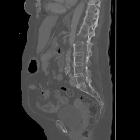

chalk stick fracture

Chalk stick, also known as carrot stick fractures, are fractures of the fused spine, classically seen in ankylosing spondylitis.

They usually occur through the disco-vertebral junction in the lower cervical or upper thoracic spine.

When several contiguous segments of the spine are fused, the fused column acts as a lever arm. This places greater than normal stresses on the spine. These fractures often occur following minimal trauma due to the altered biomechanics of the spine.

Not surprisingly, it is named because of the resemblance of the fracture to breaking a chalk stick or a carrot.